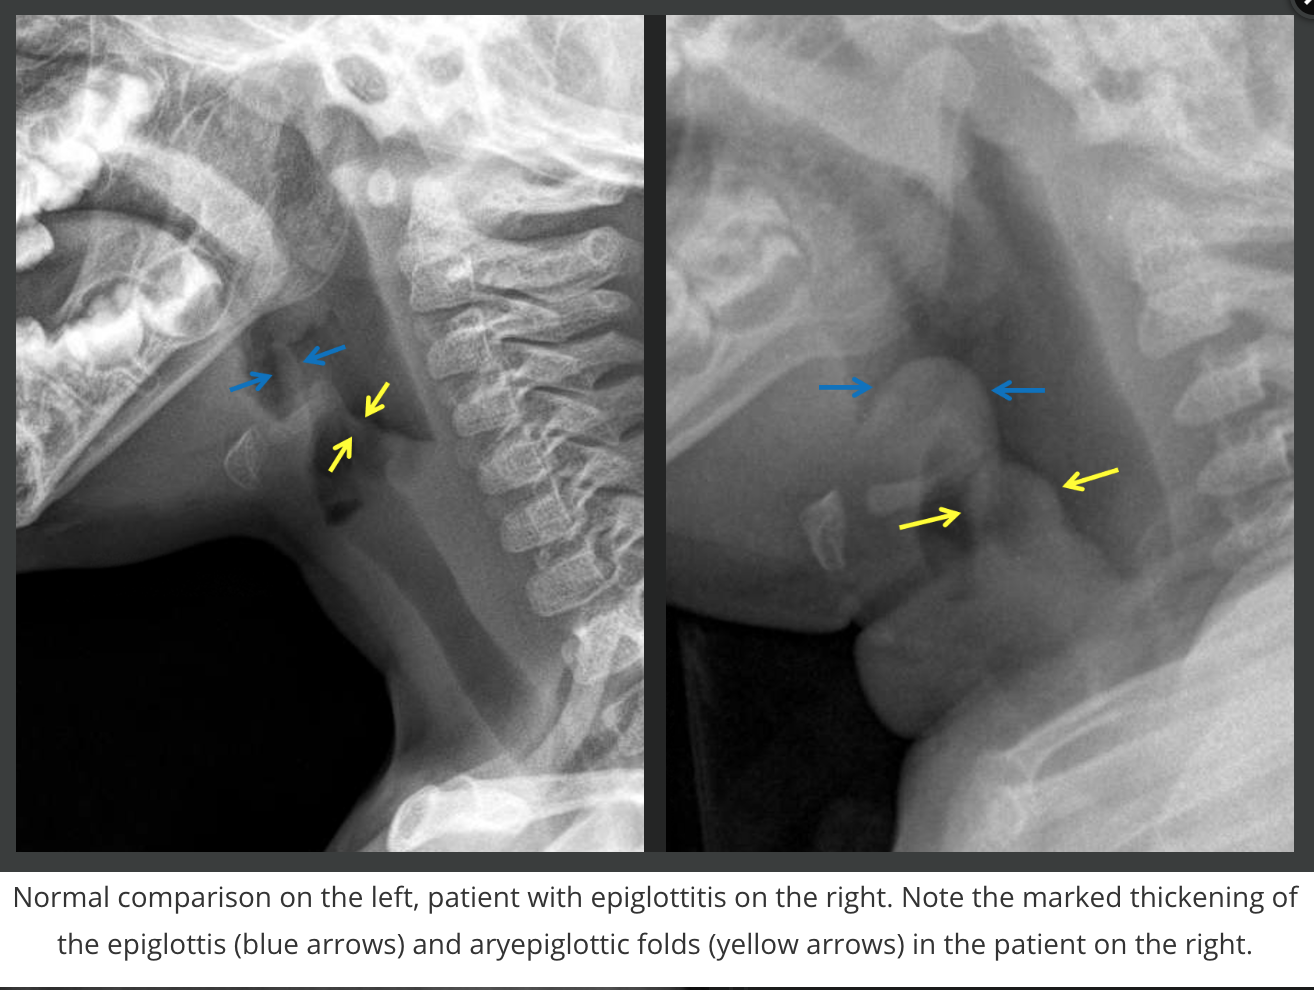

Epiglottitis

• Kids/teens >3 years old

• H-flu